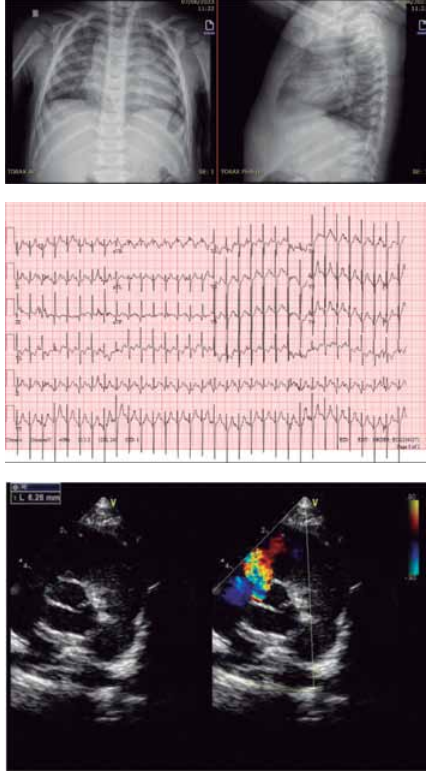

Considere as imagens a seguir.

(Arquivo pessoal; imagens usadas com autorização)

Qual é o diagnóstico provável da cardiopatia congênita ilustrada pela radiografia de tórax e a figura de ecocardiograma apresentadas desse recém-nascido?